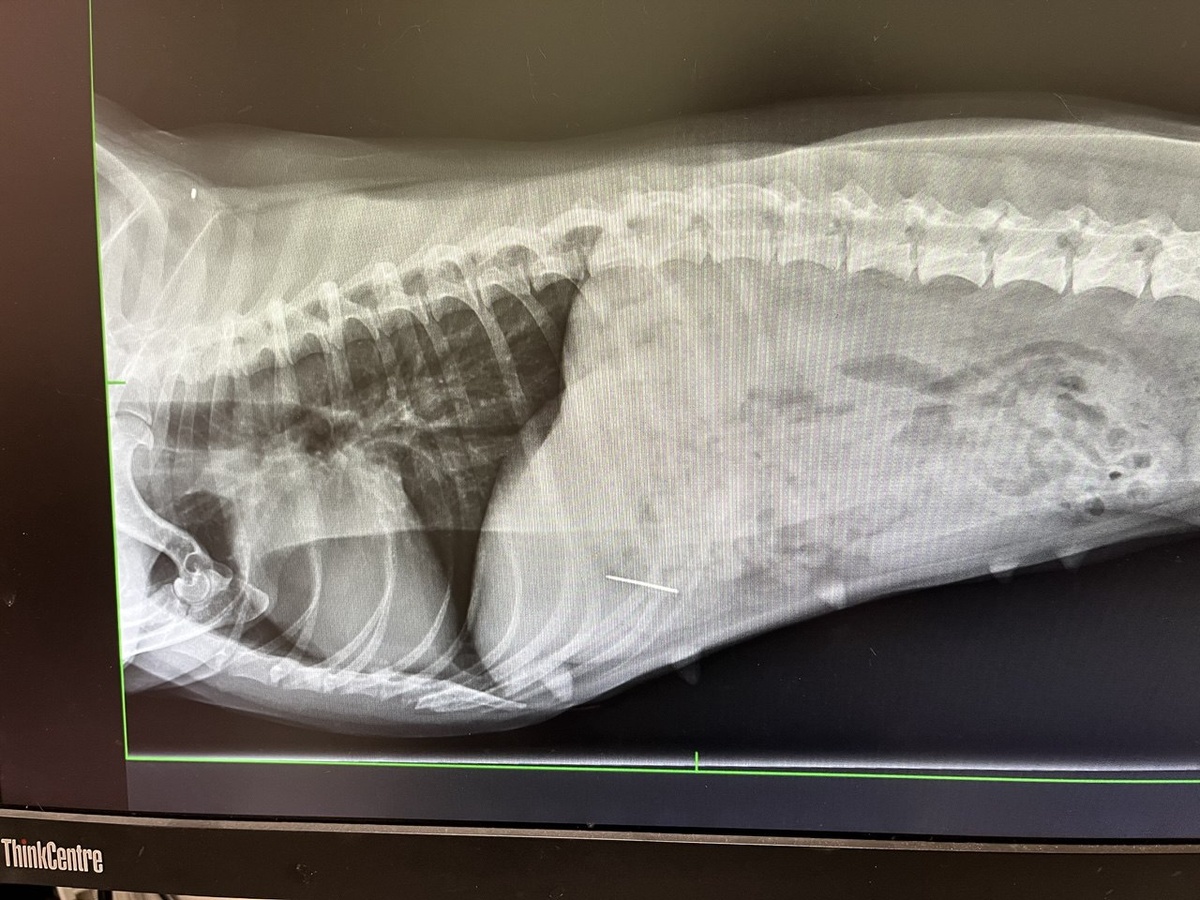

-Срочно. Гуччи проглотила булавку. Мы бежим на рентген в ближайшую клинику.

Вуаля....

Наш любимый доктор ещё и нитку там увидел, хотя владельцы уверяли, что там булавка-гвоздик, вот такая:

И таки да! Это иголка с ниткой, а не булавка! Снимаю шляпу перед Дмитрием Алексеевичем!